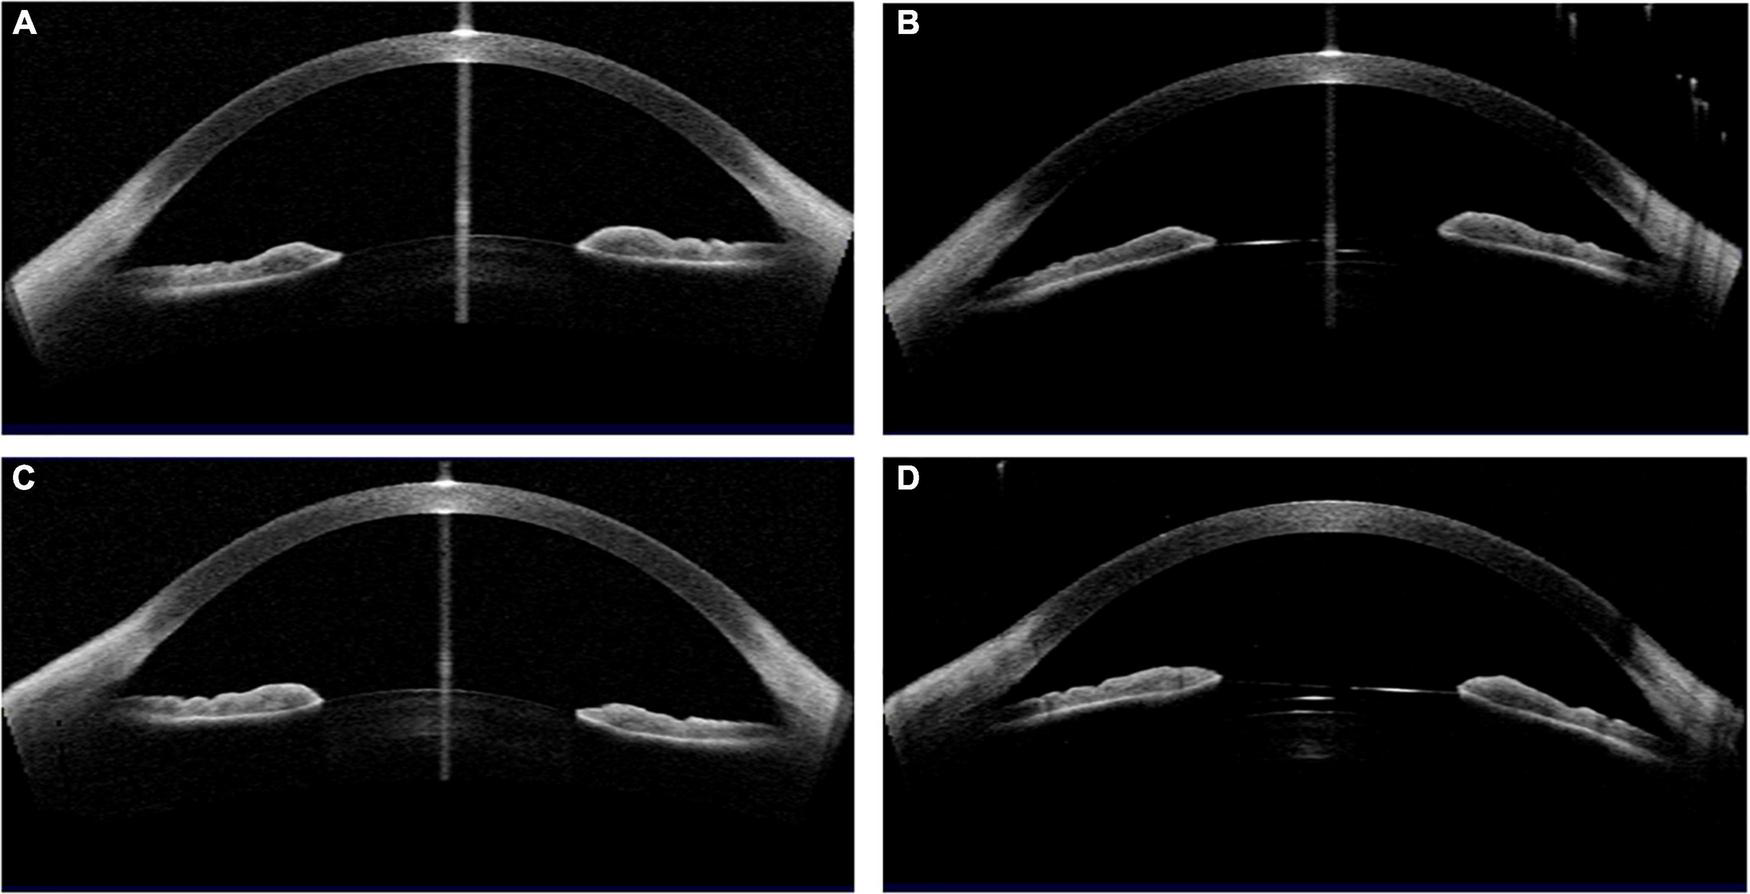

FIGURE 4

Case 1: (A,C) Concave shape iris before surgery; (B,D) low vault was shown in both eyes 1 year postoperatively. (Row 1: right eye; Row 2: left eye).